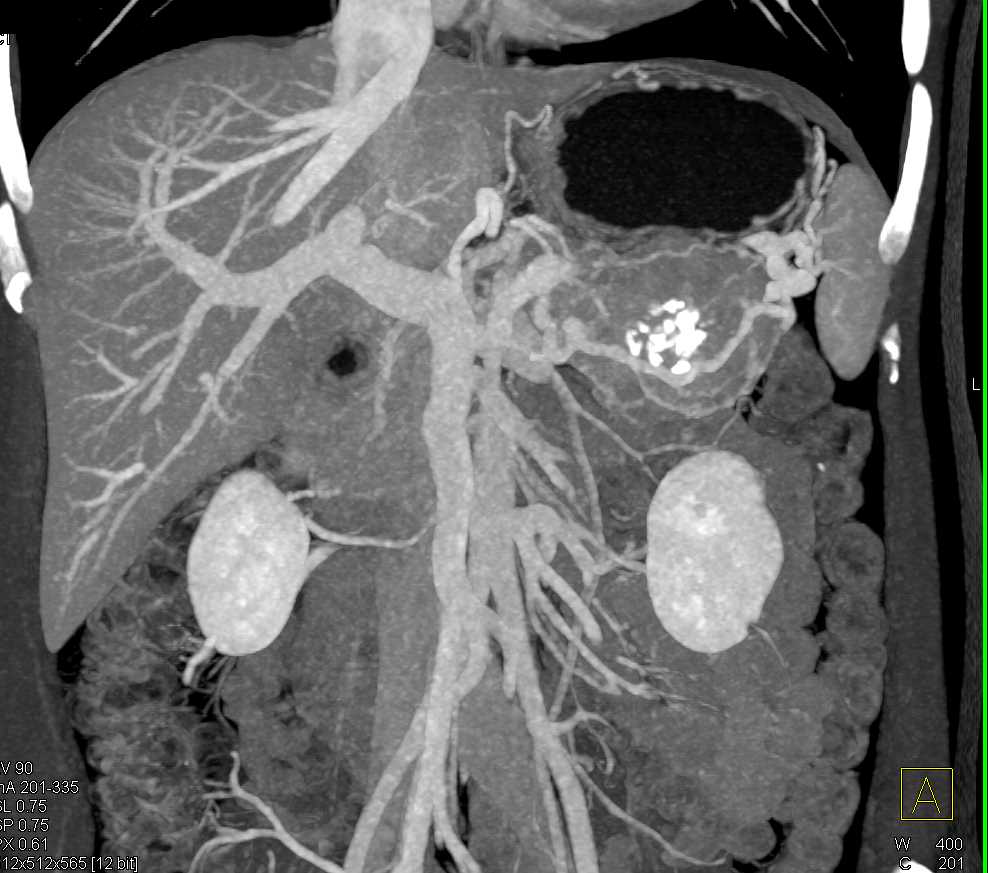

PNET Tail of the Pancreas